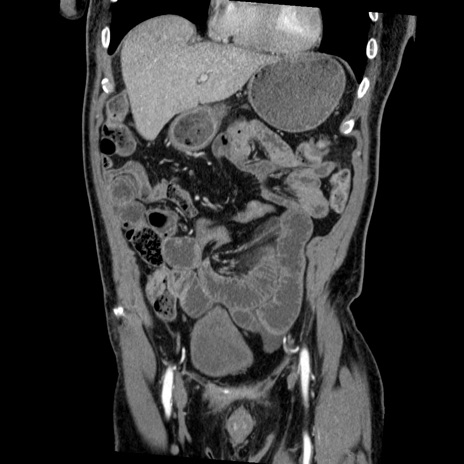

症例22(冠状断像)

【症例】50歳代男性

【主訴】腹痛

【現病歴】AVMからの被殻出血のため回復期リハ病棟入院中。 本日午後3時頃急に下腹部痛が出現した。

【既往歴】AVM、被殻出血、虫垂炎、高血圧

【身体所見】意識晴明、左半身不全麻痺、会話の理解は良好、36.5°C、腹部:膨隆、全体に板状硬、下腹部正中に圧痛点あり、反跳痛-、筋性防御不明、右下腹部にope scar

【データ】WBC 9400、CRP 0.06